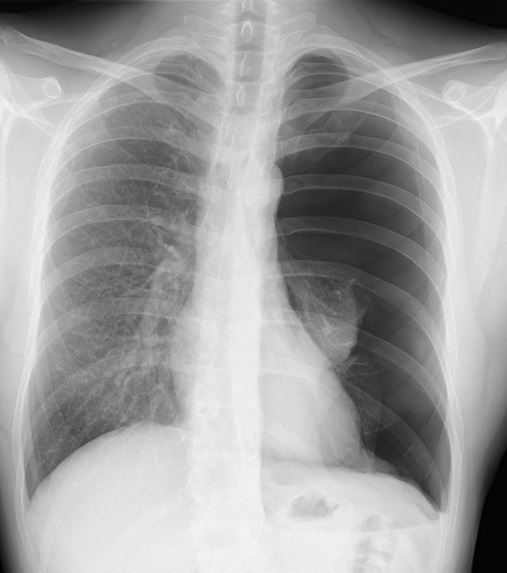

Inage radiologique PA

d'une pleumothorax totale du poumon

gauche . Poumon droit etre collabe en

moignon pres du hile ( signe direct ) .

Signe indirect de pneumothorax du poumon

gauche est image volumineuse avec aspect

ecartation de espace intercostale du

poumon , le mediastin se devier à droit

et coupole diagphrame gauche est très

bas |